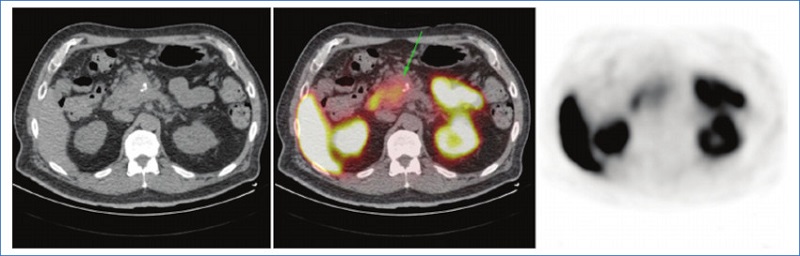

Se presenta el caso de un paciente de 62 años, con antecedente de alergia al contraste iodado, que consulta por ascenso paulatino de su antígeno prostático específico (PSA), presentando en el analítico sanguíneo un valor de 10,70 ng/ml. Se realizó una resonancia magnética (RM) multiparamétrica, la cual mostró una lesión PIRADS 4 de 15 mm localizada en el ápex derecho de la próstata en la región fibromuscular anterior. Se solicitó una biopsia de próstata que informó adenocarcinoma de próstata score de Gleason 6. Se estadificó enfermedad prostática con 18F-PET-PSMA-1007, cuyo informe reveló captación heterogénea del radio trazador con un SUVmáx de 4 en la región anterior de la próstata. Además, se observó una lesión en la porción cefálica de la glándula pancreática la cual mostró una moderada captación del trazador con un SUVmáx de 4,5 acompañada de dilatación del conducto pancreático principal (Fig. 1). Dado su antecedente de alergia al contraste iodado, se solicitó una RM de abdomen, donde se visualizó una formación en el páncreas, isointensa en secuencias ponderadas en T2 e hipoisointensa en secuencias ponderadas en T1, la cual se localizaba en la cabeza generando una compresión del conducto pancreático común (Fig. 2). Además, se constató elevación del marcador tumoral Ca 19.9, por lo cual se solicitó biopsia guiada por ecografía endoscópica, la cual informó la presencia de un adenocarcinoma moderadamente diferenciado de páncreas. Actualmente el paciente se encuentra en vigilancia activa por su adenocarcinoma de próstata y realizando quimioterapia neoadyuvante para una eventual duodenopancreatectomía.